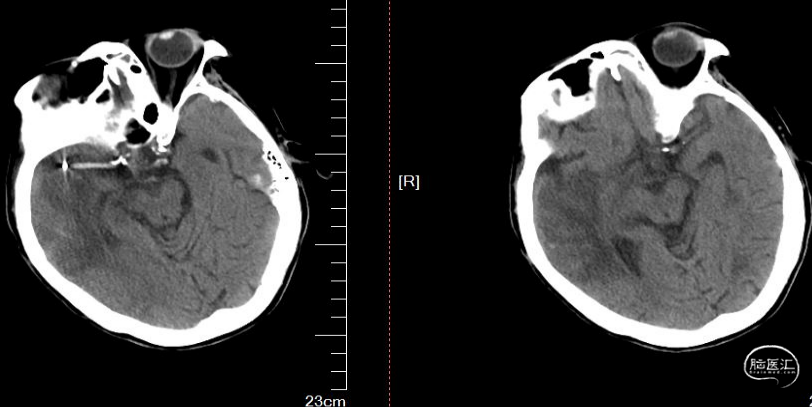

术前影像

术前CT, Aspects评分5分

术后24小时CT。

术后7天CT。